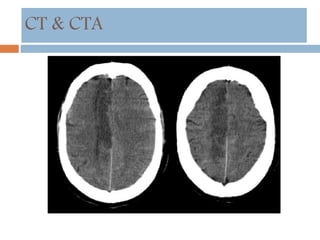

CT & CTA

 HDMCA sign

 Insular ribbon sign